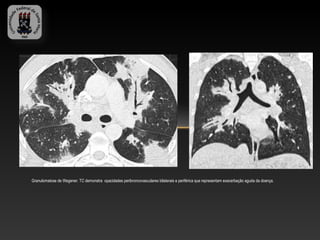

Granulomatose de Wegener. TC demonstra opacidades peribroncovasculares bilaterais e periférica que representam exacerbação aguda da doença.